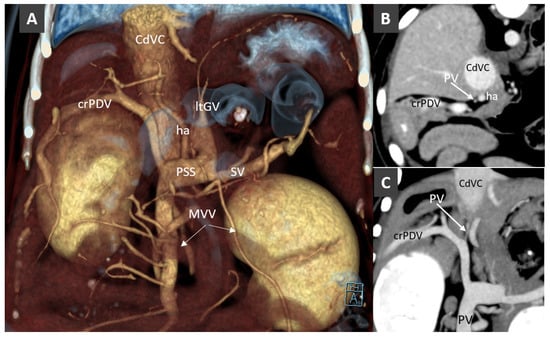

Congenital Portosystemic Shunt

3.7. Acquired Portosystemic Shunts (APSSs)